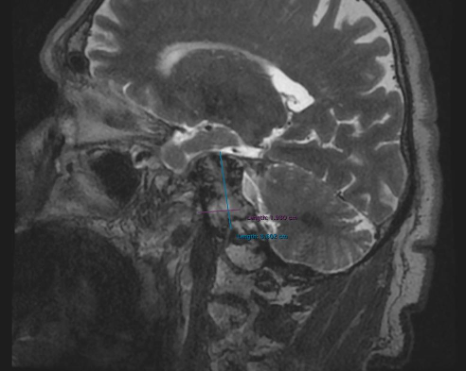

Results: Brain MRI (1,5 Tesla): MRI of the brain demonstrates a lesion in the right temporal bone region (squoma part) with mass effect on adjacent structures. The lesion measures (38х25х33 cm) and exhibits characteristics suggestive of a space-occupying process. Findings include: possible involvement of the brainstem and surrounding neurovascular structures, no evidence of acute hemorrhage, hydrocephalus, or significant midline shift.

Sagittal